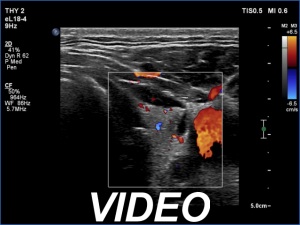

Ultrasonography. The thyroid was echonormal and had two cystic lesions in the left lobe. With higher frequency, the dorsal part of both lobes presented with hypoechoic blurred areas. With frequency decreased, these areas have disappeared.

Comment. This case illustrated the well-known inverse relation between penetrance and resolution. Better the former worst the latter and conversely. This has particular and practical importance if we examine obese patients using high-end equipment with high frequency. In such patients the obesity can significantly worsen the penetrance. This can be solved by decreasing the frequency and remove all software harmonization.